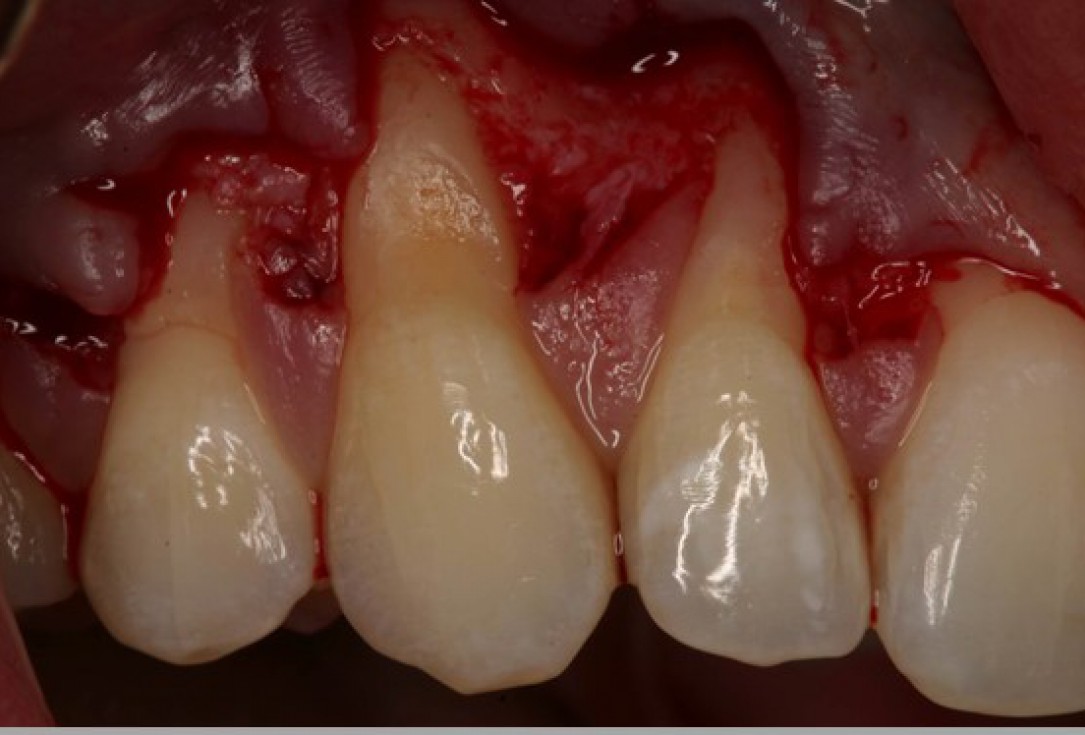

02/06 - Flap preparation according to the modified coronally advanced flap technique (Zucchelli & De Sanctis J Periodontol. 2000). Sulcular incision from tooth 11 to 15 and elevation of a splitthickness flap.Multiple gingival recessions treated with the modified coronally advanced flap in conjunction with mucoderm® - Prof. Dr. Dr. A. Kasaj